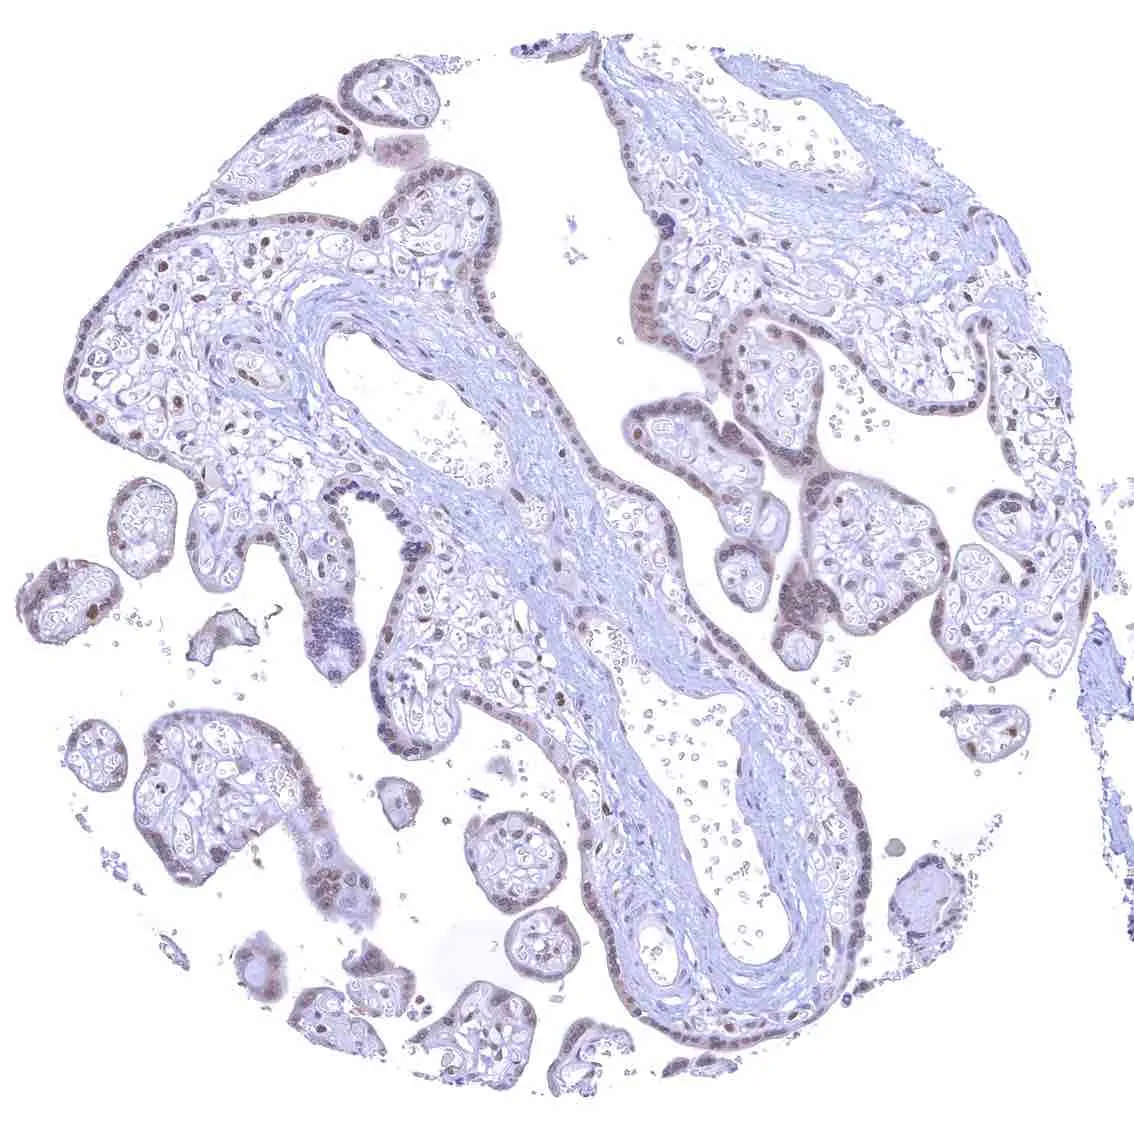

Fallopian tube, mucosa